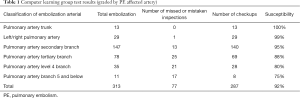

We divided 43 study groups of CTA 512×512 pictures into training sets (1,992 sheets) and test sets (192 sheets). The 101×101 embolism distribution block diagram was divided into a training set (13,144 sheets) and a test set (313 sheets), as shown in Figure 1A,B. Through the deep learning model of data learning and analysis, the final training was to obtain a prediction model. The test set was then tested. The results of the experiment are shown in Table 1.

Full table

When the prediction model analyzes the input test image, it will output a value between 0 and 1, which represents the probability that the test image contains pulmonary embolism segments. By setting a threshold, we can distinguish whether the test image contains pulmonary embolism or not. At the same threshold, the ROC curves of sensitivity and false positive are shown in Figure 2. The overall sensitivity was 0.990 (99.0%). When the average number of false positives per case was 2, the sensitivity was 0.823.